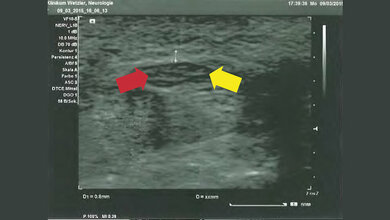

In einer aktuellen Studie der Universitätsmedizin Leipzig mit Unterstützung des Helmholtz-Instituts für Metabolismus-, Adipositas- und Gefäßforschung (HI-MAG) fanden Forscherinnen und Forscher heraus, dass die Qualität des Ultraschalls bei Leber- und Nierenuntersuchungen bei Patientinnen und Patienten mit Adipositas deutlich beeinträchtigt ist. „Die Ergebnisse zeigten: Je höher der Body-Mass-Index der Teilnehmenden war, desto schlechter war auch die Bildqualität des Ultraschalls. Außerdem wurde deutlich: Moderne Ultraschallsonden mit der sogenannten Matrixtechnologie verbessern die Qualität der Ultraschallabbildung“, erklärt Prof. Dr. Thomas Karlas, Studienleiter und korrespondierender Autor der aktuellen Publikation. Die Matrixsonden besitzen eine verbesserte Sende- und Empfangstechnologie und erreichen dadurch eine höhere Eindringtiefe in das Gewebe. Somit kann eine bessere diagnostische Genauigkeit bei Risikopatientinnen und -patienten erreicht werden. Bislang gab es noch keine ausreichende wissenschaftliche Bestätigung der Leistungsfähigkeit der Matrixsonden bei Personen mit Übergewicht.